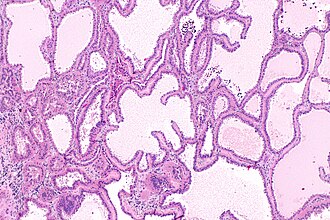

Tubulocystic renal cell carcinoma. H&E stain. | |

| LM | cysts of variable size lined by a single layer of epithelium that has a cuboidal, flat, or hobnail morphology, eosinophilic cytoplasm, large nuclei with prominent nucleoli, +/-fibrotic stroma |

Features:.[2]

- Cysts of variable size lined by a single layer of epithelium that has a:

- Cuboidal, flat, or hobnail morphology.

- Eosinophilic cytoplasm.

- Large nuclei with prominent nucleoli.

- +/-Fibrotic stroma.